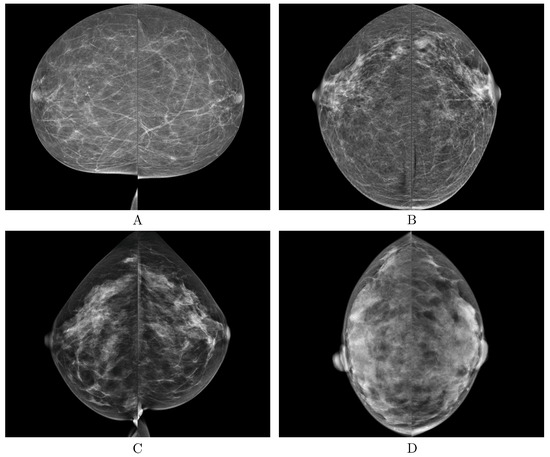

| BI-RADS Category | / |

|---|---|

| Class A | 879/3516 |

| Class B | 3212/12,848 |

| Class C | 928/3712 |

| Class D | 111/444 |

| Total | 5130/20,520 |

| Class A | 18/72 |

| Class B | 43/172 |

| Class C | 7/28 |

| Class D | 4/16 |

| Total | 72/288 |